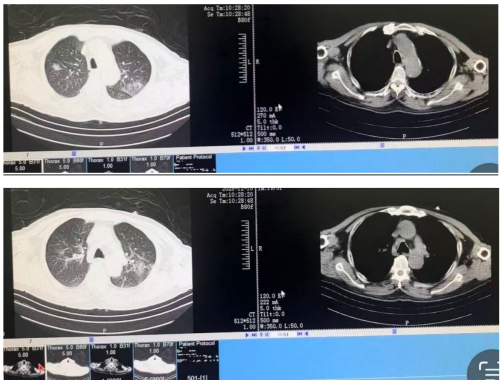

12月08日 改鼻导管吸氧3L/min

12月10日 复查CRP21mg/L,复查胸部CT较前好转,请普通病房会诊后转至普通病房继续治疗。

12月10日胸部CT: